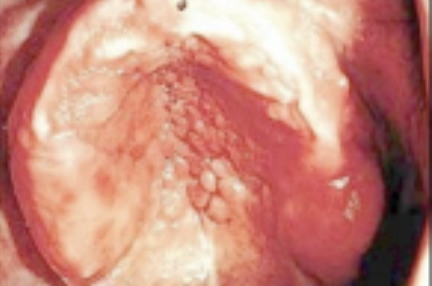

Wat is papillaire hyperplasie?

Tot de verruceuze/papillaire afwijkingen worden de afwijkingen gerekend die een uitwas zijn van de mucosale membraan. Deze afwijkingen hebben diverse verschijningsvormen met een lokale exofytische groeipotentie en kunnen variëren van enkele millimeters tot enkele centimeters. De afwijkingen kunnen overal op orale mucosa voorkomen. De oorzaak is een niet goed passende prothese of chronische candidiasis. Aan het begin is het rood en ontstoken, vervolgens oedematische slijmvliezen en tenslotte ontstaan er kenmerkende papillaire beeld. Je kan dit behandelen door de prothese aan te passen of de candidiasis aan te pakken.